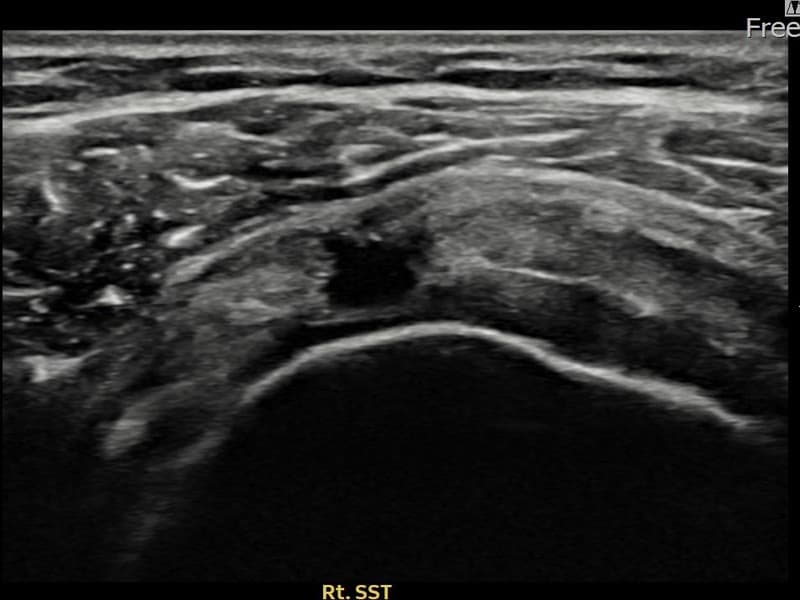

시술 전 초음파 측정 결과 파열 크기는 12mm × 7mm (힘줄 두께의 약 55% 결손)로 확인되었습니다. 시술 전 초음파에서 우측 극상근건의 광범위한 에코 단절과 힘줄 내 복합 소견이 확인되었습니다. 시술 후 초음파에서 파열 부위에 재생 조직이 형성되며 힘줄 연속성이 회복된 것이 관찰되었습니다.

50대 중반 남성 환자분으로, 우측 어깨 통증이 오래되어 파열이 상당히 진행된 상태였습니다. 다방향에서 초음파 평가를 시행한 결과 관절면측 파열이 넓게 퍼진 진행형 소견이 확인되었습니다. 파열 범위가 넓어 일반 보존 치료로는 한계가 있다고 판단하여 초음파 유도 하 축소봉합술을 시행하였습니다. 시술 후 충분한 보조기 착용 기간을 유지하고 단계적 재활을 진행하였으며, 14주 후 추적 초음파에서 파열 부위의 구조적 안정화가 확인되었습니다.